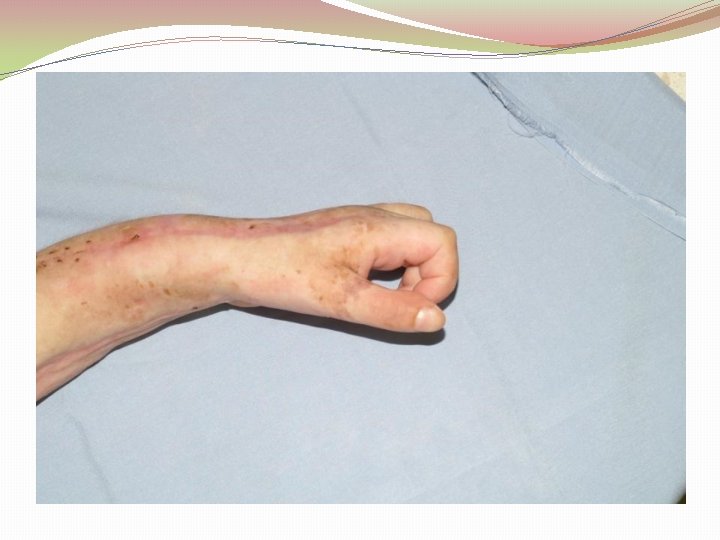

Ķirurģiska ārstēšana Osteomielīta pacientiem jāveic radikāls debridement ķirurģiski, kas ietver visu procesā iesaistīto audu rezekciju: �Mīksto audu rētas rezekcija �Cīpslu kalcinātu rezekcija �Distantu sekvestru rezekcija �Kaula rezekcija līdz vizuāli veseliem audiem – readzama punktveida asiņošana ´Paprika sign’. Bogdan Maciuceanu, Lucian Jiga, Alexandru Nistor, Jenel Marian Pastrascu, Mihail Ionac Chronic Osteomyelitis of Long Bones Timisoaral Medical Jornal, 2005